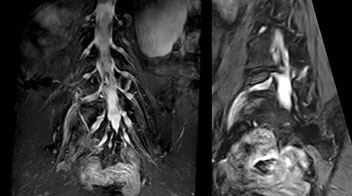

“In patients with lower extremity neurological symptoms, NerveVIEW helps us to determine the disease matching the patient’s symptoms by directly visualizing the nerves. We use the sequence mainly, when there is suspicion of intraforaminal stenosis, extraforaminal stenosis or lateral disc herniation, which is often based on routine T2- and T1-weighted images. Additionally, the excellent depiction of the course of nerves makes NerveVIEW a good navigator when applying treatment such as block therapy or surgery.”

“In such case, we would then browse through axial T2-weighted MR images slice by slice and mentally reconstruct the actual situation based on both radiculography and MRI. Fortunately, NerveVIEW can now very well show nerve courses and presence of nerve compression or edema in one single image series.” “We have often seen NerveVIEW directly depict details of the nerve compression that were not observed by radiculography. Therefore, we think that with NerveVIEW we can reduce the number of invasive examinations, especially for some patients with lumbar plexus symptoms.”

“Before NerveVIEW, diagnosis by MRI alone was sometimes difficult, unless there was a strong suspicion based on clinical symptoms,” says Shoji Yabuki, MD, DMSc, Orthopedic surgeon at Fukushima Medical University School of Medicine. “This is why we routinely perform selective lumbosacral radiculography (nerve root block) and x-ray in such cases. However, radiculography can only depict nerves as far as the contrast agent reaches. When a nerve is distorted by compression, the contrast agent will not pass through this compressed area, preventing us from evaluating the full nerve compression.”

The key concept in MR neurography, Dr. Yabuki stresses, is the ability to directly visualize spinal nerves, versus inferring the presence of pathology indirectly. “Before NerveVIEW, we estimated compression of the nerve by looking for the presence or absence of fat signal on other MR images,” he says.

“For example, in sagittal images, when the presence of fat is observed in the intervertebral foramen, it suggests that there is a margin around the nerve. Similarly, the absence of fat indicates that the nerve is being compressed. So, we used to deduce nerve compression indirectly. With NerveVIEW, however, we can observe the condition of the nerves directly, regardless of the presence or absence of fat. We always prefer such direct observation of anatomy over having to make an inference about it.”

Distinguishing typical from atypical herniation informs the surgeon

“Although symptoms of typical disc herniation and atypical hernia are very similar, the actual site of herniation is different. It is therefore important to characterize the nerve’s condition both inside and outside of the intervertebral foramina. “Conversely, if we see no abnormality in NerveVIEW, we can assume at least that there is no severe condition that requires surgery. Like this, it can help us avoid unnecessary surgery. NerveVIEW can have a tremendous impact in this way.”

“NerveVIEW is really useful for those cases where a nerve disorder is strongly suspected based on the clinical examination but our regular MRI images do not show any findings. These atypical herniations and spinal canal stenosis, occurring in 5% to 15% of the total lumbar herniation/stenosis cases are our main target when using NerveVIEW,” says Dr. Yabuki.